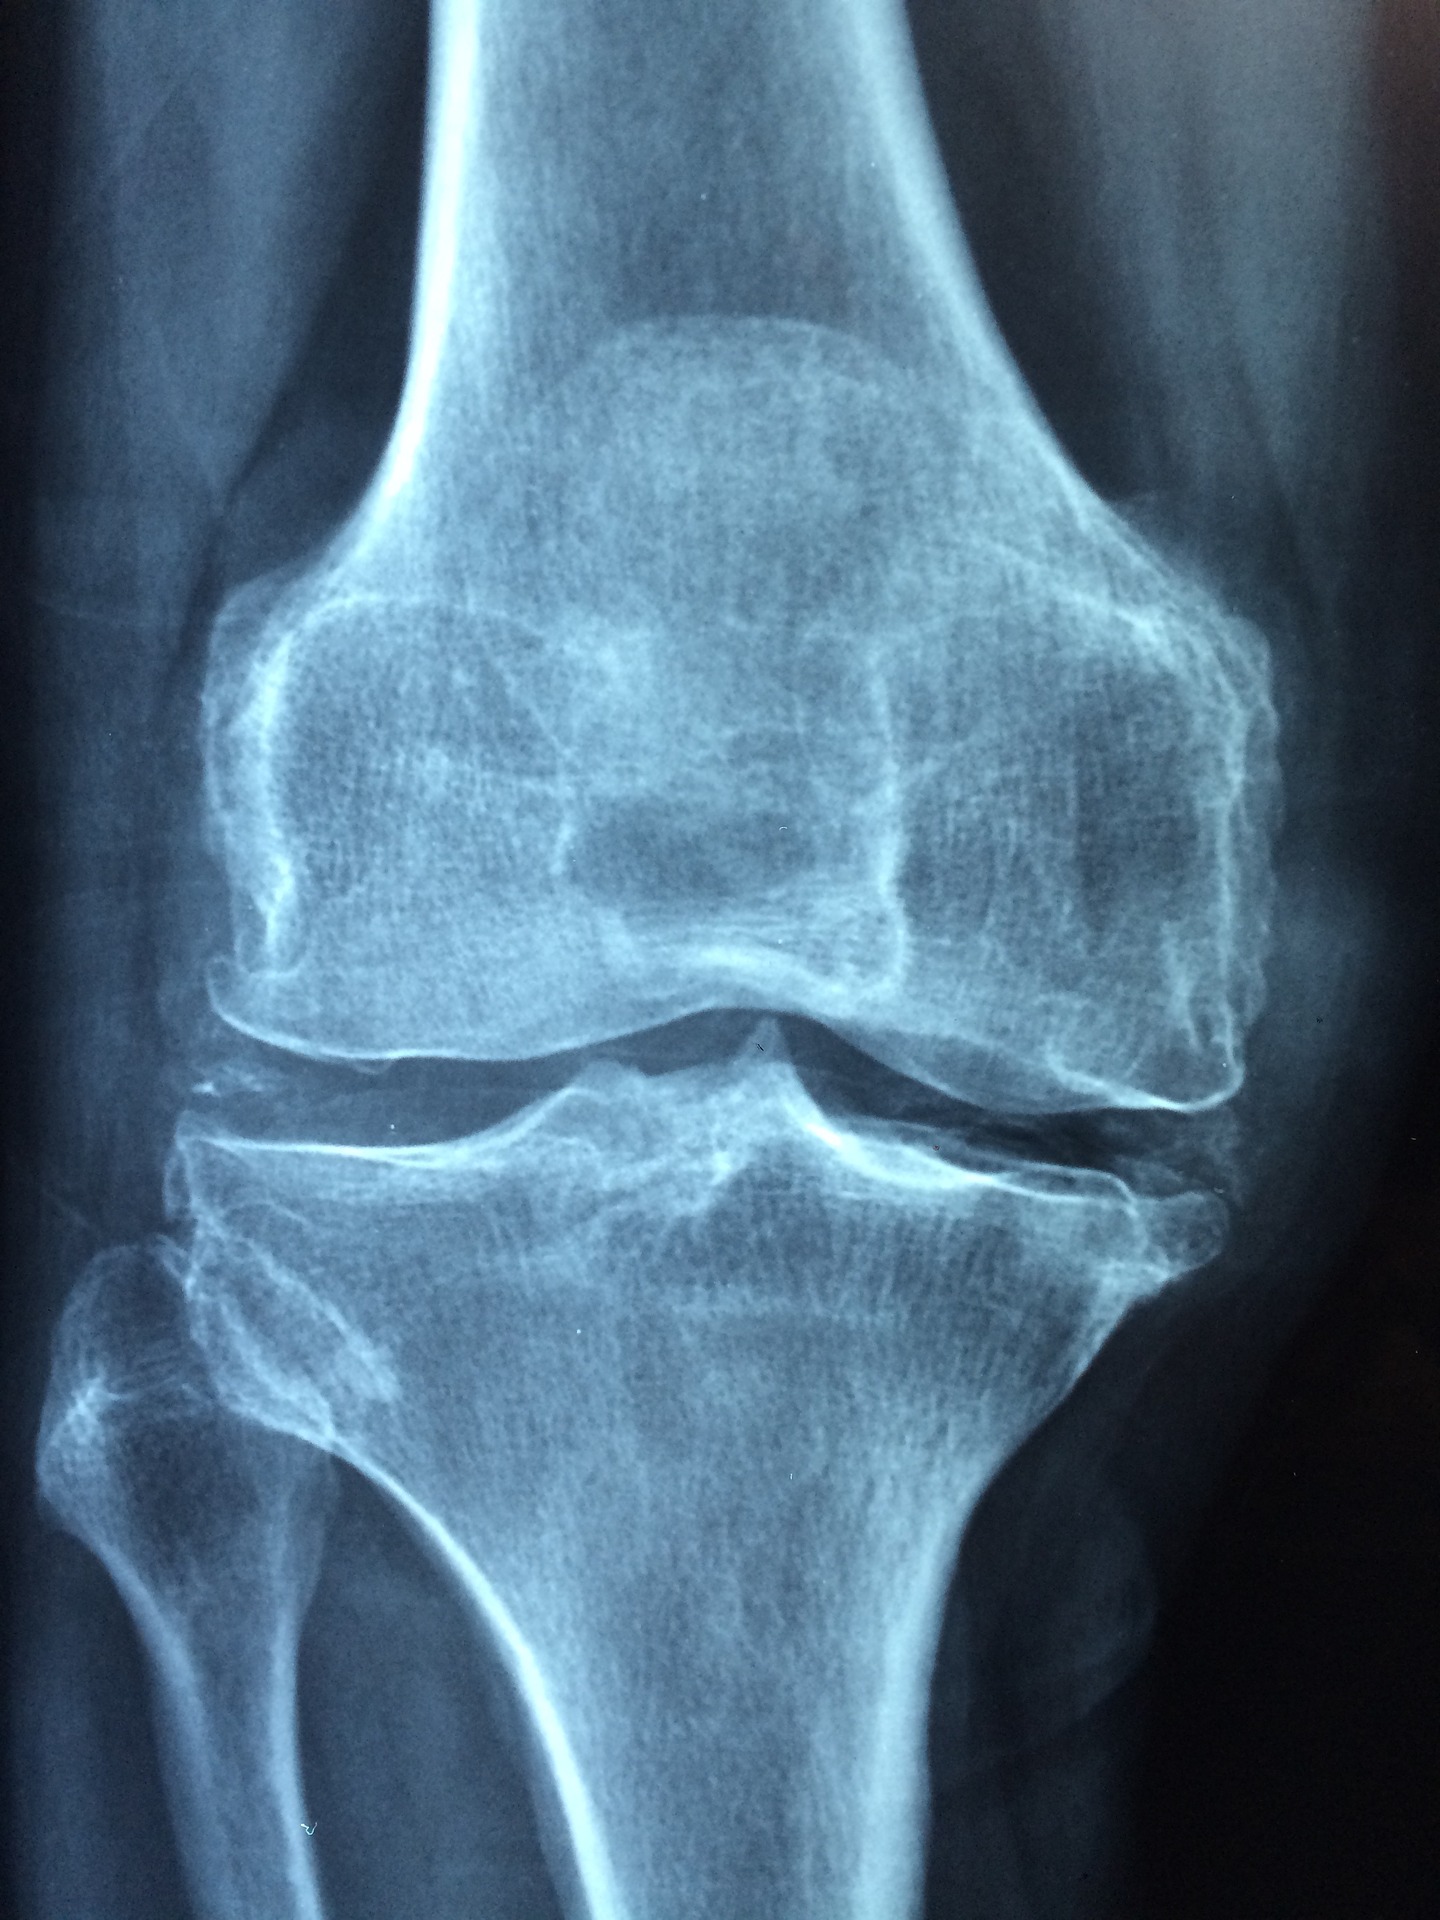

8. 골다공증

폐경기 여성들은 골밀도 검사를 통해

뼈에 도움되는

칼슘제를 먹곤하는데

식초는 칼슘이 체내에 잘 흡수되도록

하기 때문에 골다공증 예방에 좋다고 해요.

그렇기 때문에 칼슘식품과 함께 먹으며

효과가 뛰어나다고 합니다.